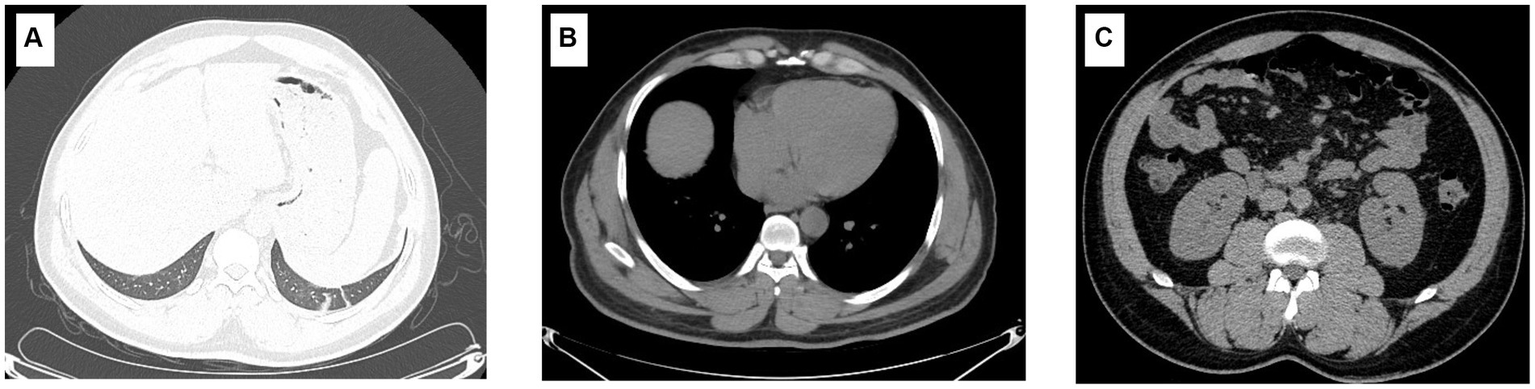

Physical examination on admission showed that body temperature, pulse rate, respiratory rate, and blood pressure were 38.6°C, 86 beats/min, 23 beats/min, and 110/66 mmHg, respectively, together with slight pharyngeal congestion. Laboratory examination during hospitalization indicated leukocytosis (peak value 13.15 × 109; normal value 3.7–9.15 × 109 cell/L), thrombocytopenia (nadir value 18 × 109; normal value 85–303 × 109 cell/L), and renal injury with an elevated level of creatine (Cr) (peak value 315.1; normal value 70–115 μmol/L), urea (peak value 27.1; normal value 1.7–8.3 mmol/L), and uric acid (UA) (peak value 684.2; normal value 204–416 μmol/L). Furthermore, overexpression of interleukin-6, procalcitonin, and B-type natriuretic peptide was also observed, which indicated inflammation and cardiovascular injury to some extent (Table 1). Besides, the abnormality of CD8+ T lymphocytes, B and natural killer (NK) cells were also found. Chest computer tomography (CT) scan showed a few inflammatory cords in the lower lobe of the left lung as well as the middle lobe of the right lung but with no further abnormality (Figure 1).

Figure 1

Imaging characteristics of the patient. The imaging findings show a few inflammatory cords in the lower lobe of the left lung as well as the middle lobe of the right lung (A); however, the typical symptoms of HFRS, including renal edema, perirenal fascial edema, pleural effusion, and pericardial effusion, were not found (B,C).